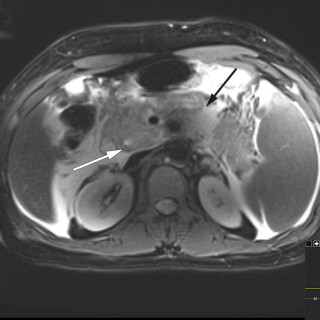

Kronisk transplantat-mot-vert-sykdom er en senkomplikasjon etter allogen stamcelletransplantasjon, og medfører kronisk inflammasjon og fibrose i forskjellige organer på grunn av feil regulering av donors immunceller. Sykdommen kan forekomme i alle organer, men sees hyppigst i hud, øyne, munnhule, gastrointestinaltraktus, genitalia, lunger, muskler, fascier og ledd. Kronisk transplantat-mot-vert-sykdom er assosiert med betydelig sykelighet og dødelighet, og behandling krever tett samarbeid mellom forskjellige deler av spesialisthelsetjenesten. Vi gir i denne artikkelen en klinisk oversikt over...